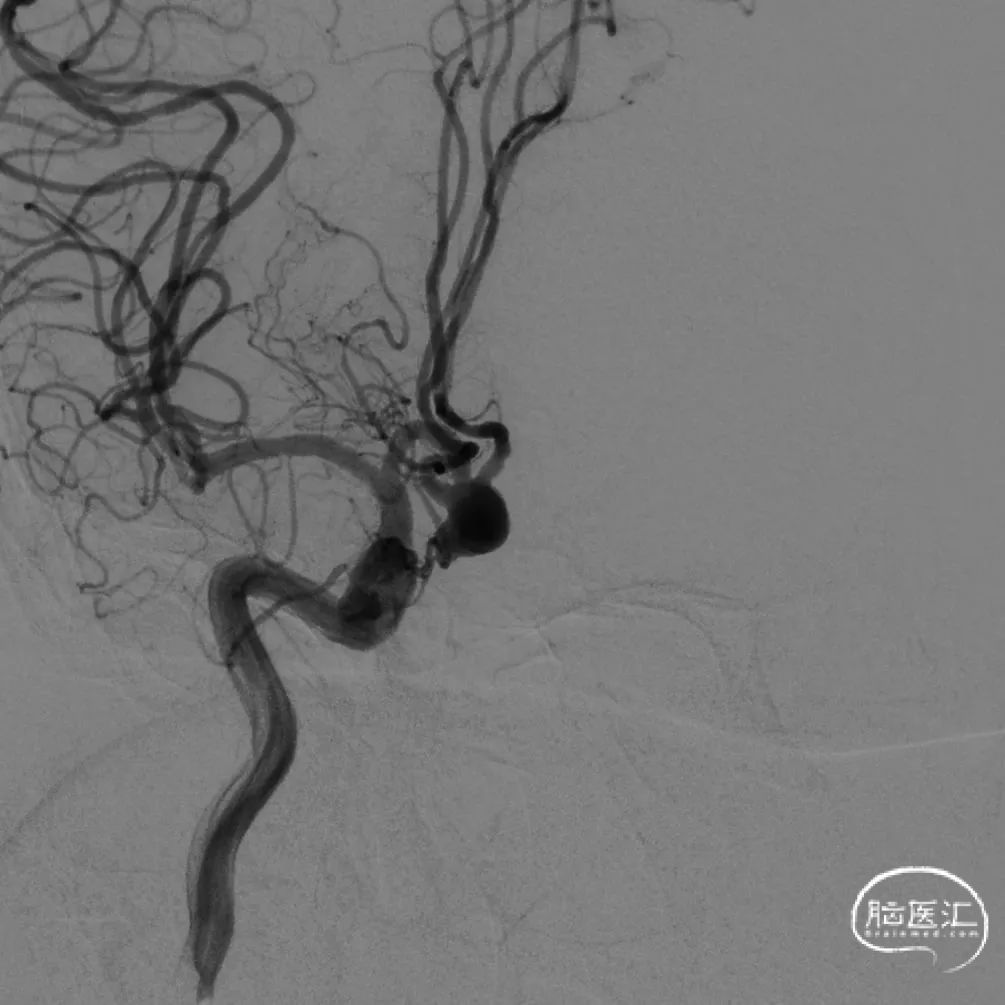

术后情况

造影示“T”型支架左侧Atlas支架 3mm*15mm 、右侧 Atlas支架 4mm*21mm,动脉瘤致密栓塞,不显影。双侧A2段显影良好。

Atlas支架是低剖面,使用0.017"微导管输送。当栓塞系统需要三套同时在A1段内存在时,可以减少动脉管腔的血流阻碍效应。另外相比其他支架,需要0.021"甚至0.027"导管输送,在动脉瘤内成袢时有较低的动脉瘤壁压力,可以减少动脉瘤破裂出血可能性,减少灾难性结局的发生。

Atlas支架是激光雕刻开环支架,在不同直径动脉内释放时,短缩及延长非常微小。可以在释放之前,准确预估其完全放开后尾端的位置,支架组合能否形成完美“T”型,完全覆盖动脉瘤颈部非常重要。

在做“T”型支架时,两条支架释放的先后顺序各有千秋。本病例是先释放“竖”后“横”,这样可以是使“竖”支架尾端不受干扰地充分张开,“横”支架和前者充分贴合。